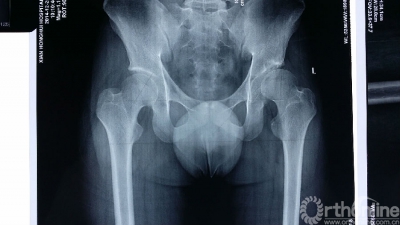

小赵今年20岁,因为髋臼发育不良并骨关节炎辗转多家省内外的大医院求诊,但专家们的回答却接近一致:要么现在做关节置换,要么“将就”到难以忍受的时候再做关节置换。人工关节置换可暂时获得疼痛缓解和行走功能,但随着时间的推移,不可避免的二次甚至三次翻修手术让20岁的小赵怎么也乐观不起来。抱着最后一线希望他慕名来到姚建锋副院长的门诊求治,姚院长和马建兵主任组织关节外科膝关节病区全科医生经过反复讨论,决定为小赵实施难度极大但疗效最好的髋臼周围截骨术(即Ganz截骨术),尽可能长久地保住属于他自己的髋关节。

Ganz截骨术是1983年由瑞士伯尔尼医院的Ganz医生开创的髋臼周围截骨术,因为难度高,风险大,被形容为骨科手术领域的“珠穆朗玛峰”。用通俗的话来说,正常髋关节的髋臼就像一顶帽子,股骨头就像脑袋,发育不良的髋臼就像帽子歪戴着,在不知不觉中将髋关节磨坏。Ganz截骨术就是把戴歪了的帽子正过来,改变了髋臼覆盖的方向,增加了髋关节对股骨头的覆盖面积,使得年轻的髋臼发育不良的患者大大延缓甚至免于人工关节置换。但迄今为止国内只有少数几家医院开展这项手术,在西北五省更是鲜有报道,而这也将是西安市红会医院开展的第一例。

术前,专家们利用数字骨科实验室中3D打印技术打印出1:1的骨盆模型,并在骨盆模型上完成预截骨。在姚建锋副院长耐心细致的的指导下,得益于充分细致的术前计划,马建兵主任的手术小组在短短两小时之内便顺利完成了Ganz截骨术,术中失血量也大大低于预期。现在患者已安全度过围手术期,正在积极康复训练,预计2-3个月之后,患者便可行走自如。